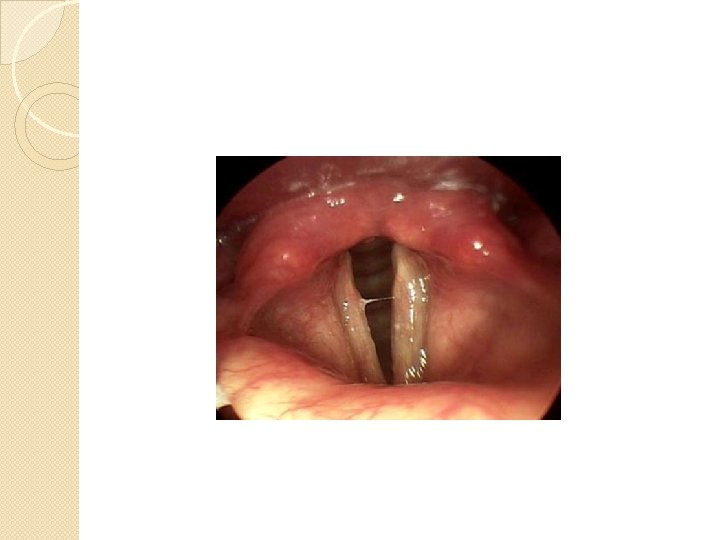

Vocal cords �Their outer edges are attached to muscle in the larynx while their inner edges are free. �If the back end of the vocal folds are held apart, a triangular space opens up between them. �The space is called glottis.

Voiceless

Voiced

Whisper

Creaky